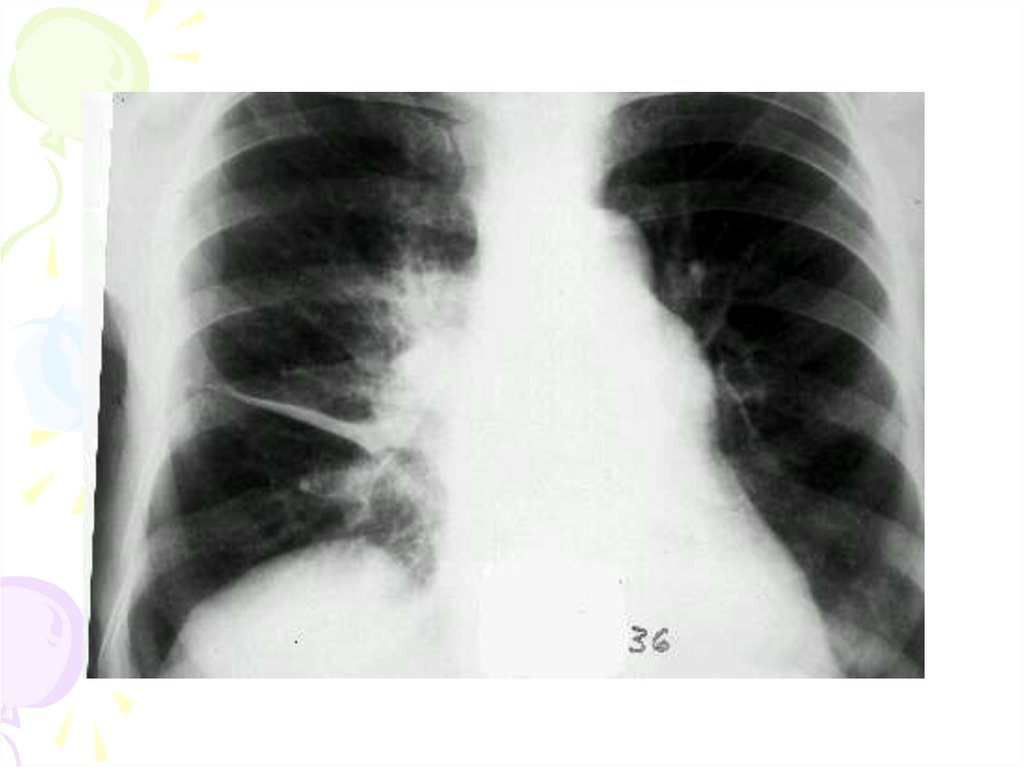

крупозная пневмония

Температура тела повышается до 39-40оС, озноб, боль в грудной

клетке, боль в правой части живота, влажный кашель (иногда со

«ржавой» мокротой), одышку.

При осмотре состояние тяжелое. Отмечаются признаки

интоксикации и дыхательной недостаточности, отставание при

дыхании пораженной стороны грудной клетки, цианоз, иногда

достигающий значительной степени. Выявляется покраснение щеки на

стороне поражения, герпетические высыпания на носу и губах.

Нередко больные принимают вынужденное положение в постели (на

больном боку).

Пальпаторно удается определить усиление голосового дрожания

на пораженной стороне.

При перкуссии выслушивается укорочение перкуторного звука,

соответствующее границам пораженной доли.

При аускультации характерно ослабление дыхания, нередко оно

становится бронхиальным. Обязательным признаком является

крепитация, которая изменяется в зависимости от стадии

заболевания. Бронхофония усилена.

19.

Клиника крупозной

пневмонии

Выявляются изменения со стороны сердца, печени,

почек, селезенки и других органов.

Рентгенологически отмечаются гомогенные

затемнения, которые занимают долю легкого. Нередко

определяются инфильтлативные изменения с нечетными

контурами.

Характерны изменения крови, лейкоцитоз со

сдвигом формулы влево, повышение СОЭ до 20 –

40мм/ч.

Различают следующие формы атипичного течения

крупозной пневмонии у детей:

- Менингеальный тип

- Абдоминальная форма

- Абортивная форма

20.